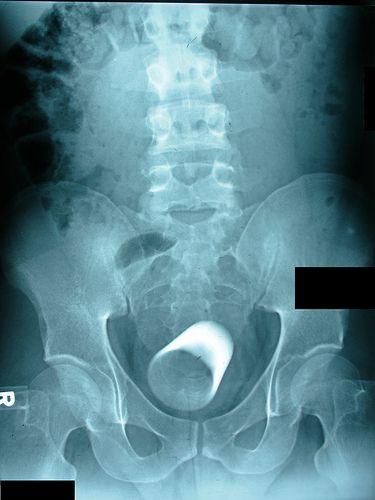

Рюмка в заднем проходе мужчины